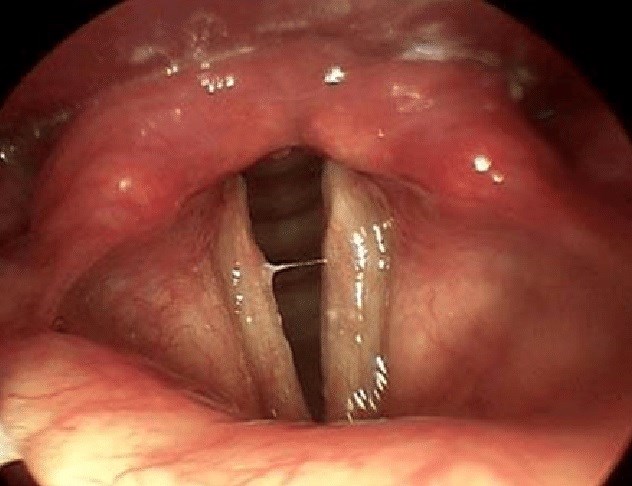

Классическая эндоскопическая картина при гортанно-глоточном забросе

- эритема черпалонадгортанной области;

- отек задней комиссуры и межчерпаловидного пространства;

- атрофия или гиперкератоз голосовых складок;

- гиперемия подскладочного пространства и первых колец трахеи;

- скопление слизи в грушевидных карманах.

Ларингоскопическая картина: отмечается сухость слизистой оболочки гортаноглотки, отечность голосовых складок, яркая гиперемия черпаловидных хрящей.

Ларингоскопия до начала терапии ИПП в течение 2 мес (видео)

Ларингоскопическая картина через 1 месяц

По словам пациента, прекращение кашля произошло на 3-и сутки терапии.